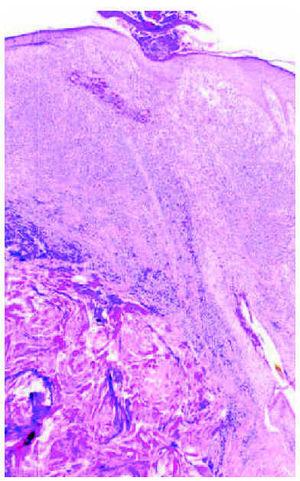

Un varón colombiano sano de 24 años consultó por lesiones en cuero cabelludo y nuca de 5 años de evolución. Tenía la costumbre de afeitarse la región de la nuca cada 15 o 20 días. La exploración reveló múltiples pápulas y papulopústulas de aspecto fibrótico en la nuca, así como nódulos inflamatorios cicatrizales o queloideos, supurativos en ocasiones, que se extendían por la región occipital del cuero cabelludo (fig. 4). La histopatología de una de estas lesiones queloideas correspondió a una foliculitis profunda aguda y crónica, con abundantes células plasmáticas y algunas células gigantes de cuerpo extraño, que comenzaba a destruir la pared folicular (fig. 5). La analítica habitual fue normal. El proceso empeoró progresivamente, con extensión del componente inflamatorio-supurativo hacia la región parietal posterior y vértex. Diversos antibióticos orales (rifampicina, minociclina y ciprofloxacino) fueron ineficaces. El paciente rehusó tratamiento con retinoides orales.

Fig. 5.--Foliculitis profunda con abundantes células plasmáticas que inicia la destrucción folicular. (Hematoxilina-eosina, x40.)